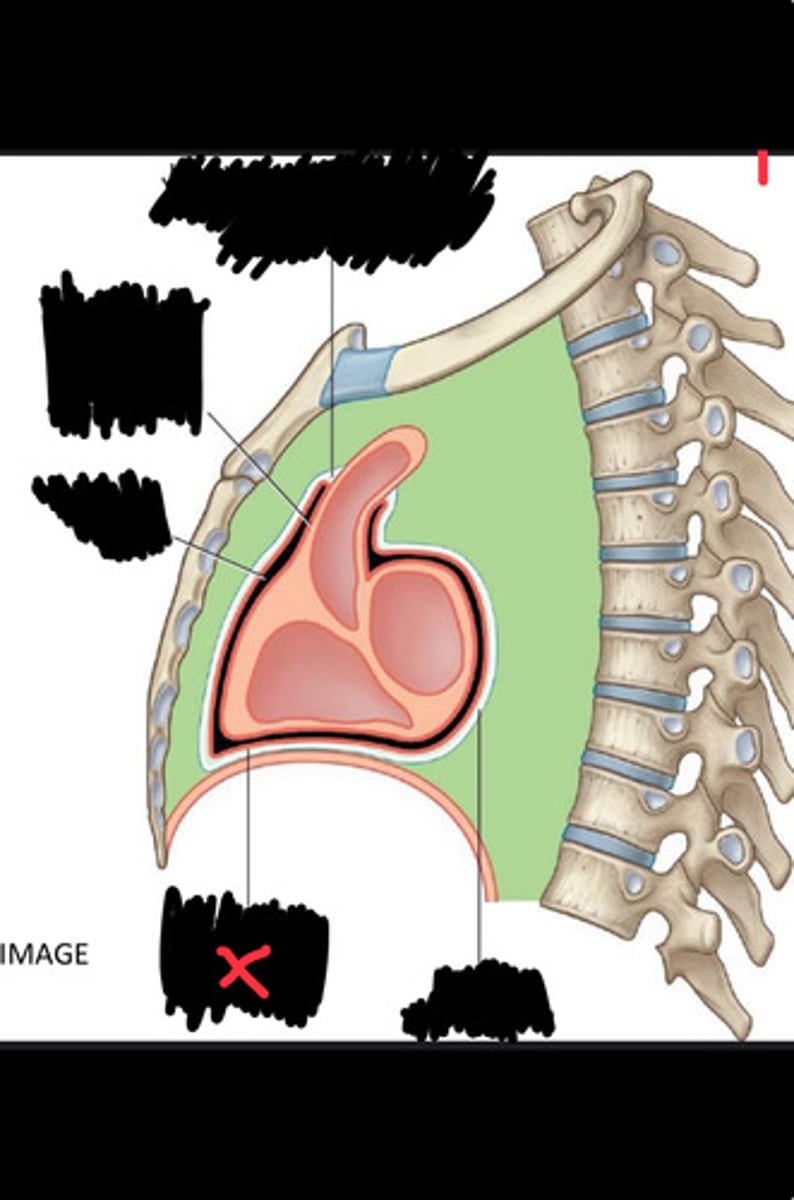

Fibrous pericardium

Parietal layer of serous pericardium

Pericardial cavity

Visceral layer of serous pericardium

Junction between fibrous pericardium and adventitia

Heart

Thoracic aorta

Rib 1